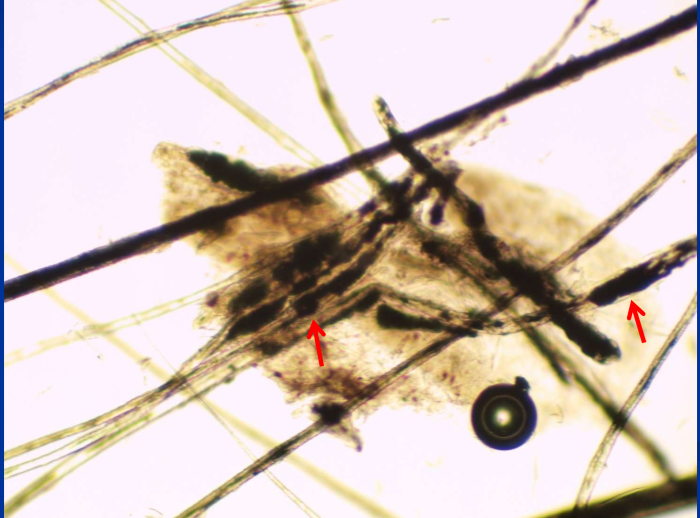

Melanin clumps in hair shafts (color dilution alopecia)

Melanin clumping on trichogram